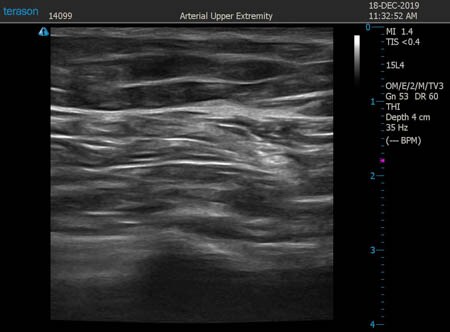

いつものように3Dタッチビュー(超音波)で

皮下脂肪層を評価してみましょう。

左太もも前面。